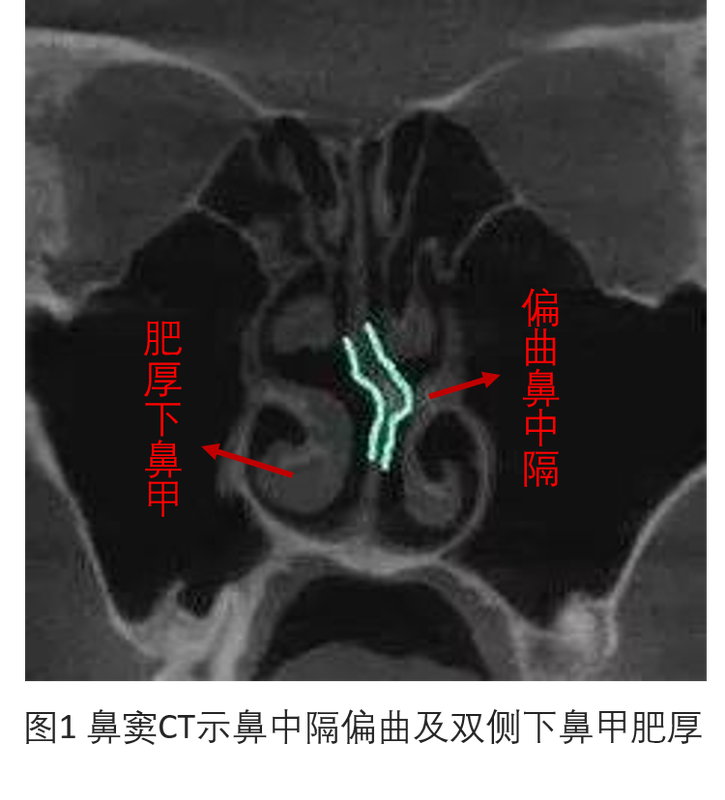

??我們在出門診的時(shí)候會(huì)經(jīng)??吹揭?yàn)楸亲硬煌鈦砜床〉幕颊?,他們癥狀大多是一側(cè)或雙側(cè)鼻腔不通氣,有的伴隨流鼻涕,打噴嚏,有的會(huì)有頭痛的癥狀,有的有間斷鼻出血的癥狀,還有一部分患者沒有任何明顯的癥狀,只是覺得整天昏昏沉沉的,頭腦不太清醒……其實(shí),這些癥狀絕大多數(shù)情況下是由一種常見的耳鼻咽喉科疾病引起的,我們稱之為:“鼻中隔偏曲、慢性鼻炎”。那么究竟什么是“鼻中隔偏曲、慢性鼻炎”呢?請看以下圖片??通過以上圖片,相信大家會(huì)有一個(gè)直觀的認(rèn)識,鼻中隔偏曲會(huì)導(dǎo)致兩側(cè)鼻腔的空間不對稱,引起兩側(cè)通氣氣流不順暢,導(dǎo)致患者鼻子不通氣,慢性鼻炎會(huì)刺激下鼻甲肥厚,進(jìn)而加重鼻塞的癥狀??赡軙?huì)有人提出疑問,比如說,鼻中隔偏向右側(cè),那么右側(cè)鼻腔變窄,左側(cè)鼻腔應(yīng)該相對通暢,至少左側(cè)鼻孔是通氣的啊?答案是,鼻中隔偏向右側(cè)會(huì)導(dǎo)致左側(cè)下鼻甲代償性肥厚,左側(cè)鼻腔也會(huì)相對變窄,所以兩邊鼻子都不通氣,所以會(huì)出現(xiàn)有的鼻中隔偏曲患者兩邊鼻子都不通氣,或者是兩邊交替性不通氣。因此,鼻中隔偏曲和慢性鼻炎常常是相伴隨的疾病。那么,“鼻中隔偏曲”具體指的是什么?是什么原因?qū)е碌???yīng)該怎么治療呢?接下來,我為大家詳細(xì)介紹一下鼻中隔偏曲的相關(guān)知識。一、鼻中隔是什么?鼻中隔把鼻腔分成左右兩部分的組織。由骨、軟骨和黏膜構(gòu)成。襯以粘膜和皮膚。鼻中隔分其為左右二腔,前方經(jīng)鼻孔通外界,后方經(jīng)鼻后孔通咽喉。二、鼻中隔偏曲是什么?鼻中隔偏曲(deviationofnasalseptum)是指鼻中隔偏離中線且引起臨床癥狀的一種鼻內(nèi)畸型。事實(shí)上大多數(shù)人的鼻中隔都有程度不同的偏曲,但是否引起鼻部癥狀,常取決于下列因素:①偏曲的程度和形式,如有的呈明顯局部突起,該部正處于鼻瓣區(qū);②鼻甲骨氣化程度;③梨狀孔外側(cè)緣骨質(zhì)或鼻瓣區(qū)軟骨有否畸形等。三.什么原因?qū)е卤侵懈羝?.外傷外傷是引起鼻中隔偏曲最常見的原因。當(dāng)外傷發(fā)生鼻骨骨折時(shí),常并發(fā)中隔軟骨脫位變形,甚至軟骨骨折,如不及時(shí)復(fù)位,可遺留中隔偏曲。嬰兒出生時(shí)產(chǎn)道狹窄,或因產(chǎn)鉗挾持不當(dāng),也可致中隔軟骨偏曲、脫位。2.小兒腺樣體腫大影響鼻通氣,張口呼吸代償,日久可致頜面骨發(fā)育畸形,硬腭高拱,結(jié)果使鼻腔的底部上抬,漸使中隔呈偏曲狀態(tài)。3.鼻中隔各部發(fā)育生長速度不一以至畸形,畸形易于發(fā)生在各部接合處。四.鼻中隔偏曲和慢性鼻炎有哪些癥狀?因?yàn)楸侵懈羝吐员茄壮3O喟殡S,所以將這兩者癥狀放在一起講。以下癥狀可單一出現(xiàn)也可合并出現(xiàn)。1.鼻塞可呈持續(xù)性鼻塞,如一側(cè)偏曲為單側(cè)鼻塞,若中隔呈“S”形偏曲則為雙側(cè)鼻塞。若合并慢性鼻炎,鼻塞可呈間歇性或交替性。①間歇性鼻塞:一般表現(xiàn)為白天、勞動(dòng)或運(yùn)動(dòng)時(shí)減輕,夜間、靜坐或寒冷時(shí)加重。②交替性鼻塞:側(cè)臥時(shí)位于下側(cè)的鼻腔常阻塞加重;轉(zhuǎn)臥另一側(cè)后,剛才位于上側(cè)沒有鼻塞或鼻塞較輕的鼻腔,轉(zhuǎn)到下側(cè)后出現(xiàn)鼻塞或鼻塞加重;而剛才位于下側(cè)的鼻腔鼻塞減輕。此外,嗅覺可有不同程度的減退,說話呈閉塞性鼻音。2.多涕(若合并鼻炎)常為粘液性或粘膿性,偶呈膿性。膿性者多于繼發(fā)性感染后出現(xiàn)。3.鼻出血偏曲的突起處粘膜薄脆,受吸入的氣流刺激,日久可發(fā)生刺激性炎癥而致鼻出血。此類出血多為少量,偏曲的位置多在中隔的前部。4.反射性頭痛如偏曲部分正位于中鼻甲或下鼻甲,且與鼻甲接觸甚至相抵,常引起同側(cè)頭痛,也可成為鼻部神經(jīng)痛原因之一。鼻內(nèi)滴用血管收縮劑或鼻粘膜表面麻醉后,頭痛可減輕或消失。5.臨近結(jié)構(gòu)受累癥狀若中隔偏曲部分位于中鼻道、中鼻甲相對應(yīng)處,壓迫并造成中鼻甲外移或使中鼻甲骨氣化過度、粘膜肥厚,皆可妨礙開口于中鼻道的鼻竇引流。日久可誘發(fā)鼻竇炎,分泌性中耳炎相關(guān)癥狀,如流膿涕,耳朵悶漲感,聽力下降等。6.全身癥狀有一部分患者是看高血壓疾病,冠心病來的,因?yàn)殚L期鼻塞會(huì)引起睡眠打鼾,高血壓,心臟病,在內(nèi)科長期用藥控制不是特別理想,輾轉(zhuǎn)到我們科室看病,找到疾病的源頭在鼻子,經(jīng)過手術(shù)治療后高血壓等相關(guān)疾病也同時(shí)得到了緩解。五.如何診斷鼻中隔偏曲和慢性鼻炎?前鼻鏡檢查+鼻竇冠狀位CT可明確診斷六.治療確定診斷之后,建議擇期微創(chuàng)手術(shù)治療。手術(shù)目的與原則:簡單地說,通過手術(shù)將狹窄的鼻腔空間擴(kuò)大,比如說,術(shù)前鼻腔的氣流量為雙車道,術(shù)后要達(dá)到四車道,甚至是八車道,達(dá)到徹底通氣以及減輕鼻炎癥狀的目的。七.病例分享(此患者為前幾天我做的一例手術(shù))1.患者基本情況:患者陳某,女,30歲,以“鼻塞2年”為主訴入院。伴流鼻涕,打噴嚏,偶有頭痛,平時(shí)間斷用藥,未見明顯好轉(zhuǎn),今為求手術(shù)治療來我院,門診以“鼻中隔偏曲,慢性鼻炎”收入院。2.其余情況:查體:前鼻鏡檢查可見鼻中隔左偏,雙側(cè)下鼻甲肥厚。輔助檢查:鼻竇冠狀位CT示鼻中隔左偏,棘突型,雙側(cè)下鼻甲肥厚。雙側(cè)鼻道狹窄。3.治療:鼻中隔偏曲矯正術(shù)+雙下甲消融術(shù)4.術(shù)后:術(shù)后恢復(fù)良好,雙側(cè)鼻腔通暢,患者滿意度較高。八.患者真實(shí)反饋九.鼻內(nèi)鏡下鼻中隔偏曲矯正+下鼻甲消融手術(shù)開展情況目前鼻內(nèi)鏡下鼻中隔偏曲矯正+下鼻甲消融手術(shù)是我科開展極為成熟的手術(shù),鼻內(nèi)鏡結(jié)合等離子消融技術(shù)的使用使得手術(shù)更為精準(zhǔn)化、微創(chuàng)化,手術(shù)中出血量極少,患者術(shù)后不適感大大減少,尤其是術(shù)中高科技止血材料的應(yīng)用,患者更易接受,術(shù)后恢復(fù)更快,患者滿意度極高。王錚教授所屬團(tuán)隊(duì)開展鼻內(nèi)鏡下微創(chuàng)手術(shù)多年,每年手術(shù)例數(shù)多達(dá)1000余例,手術(shù)效果良好,手術(shù)真正做到微創(chuàng)、精準(zhǔn)與個(gè)體化,獲得了廣大患者一致好評。十.王錚教授掛號就診流程王錚教授每周一和周三全天出門診,您可以在“中國醫(yī)大一院智慧醫(yī)院”微信小程序里搜索“王錚”進(jìn)入醫(yī)生主頁;或者長按下方名片中右下角的二維碼進(jìn)入王錚醫(yī)生主頁點(diǎn)擊“預(yù)約掛號”,進(jìn)行線下門診就診;或者點(diǎn)擊“網(wǎng)上復(fù)診”,進(jìn)行網(wǎng)上咨詢感謝您的閱讀!